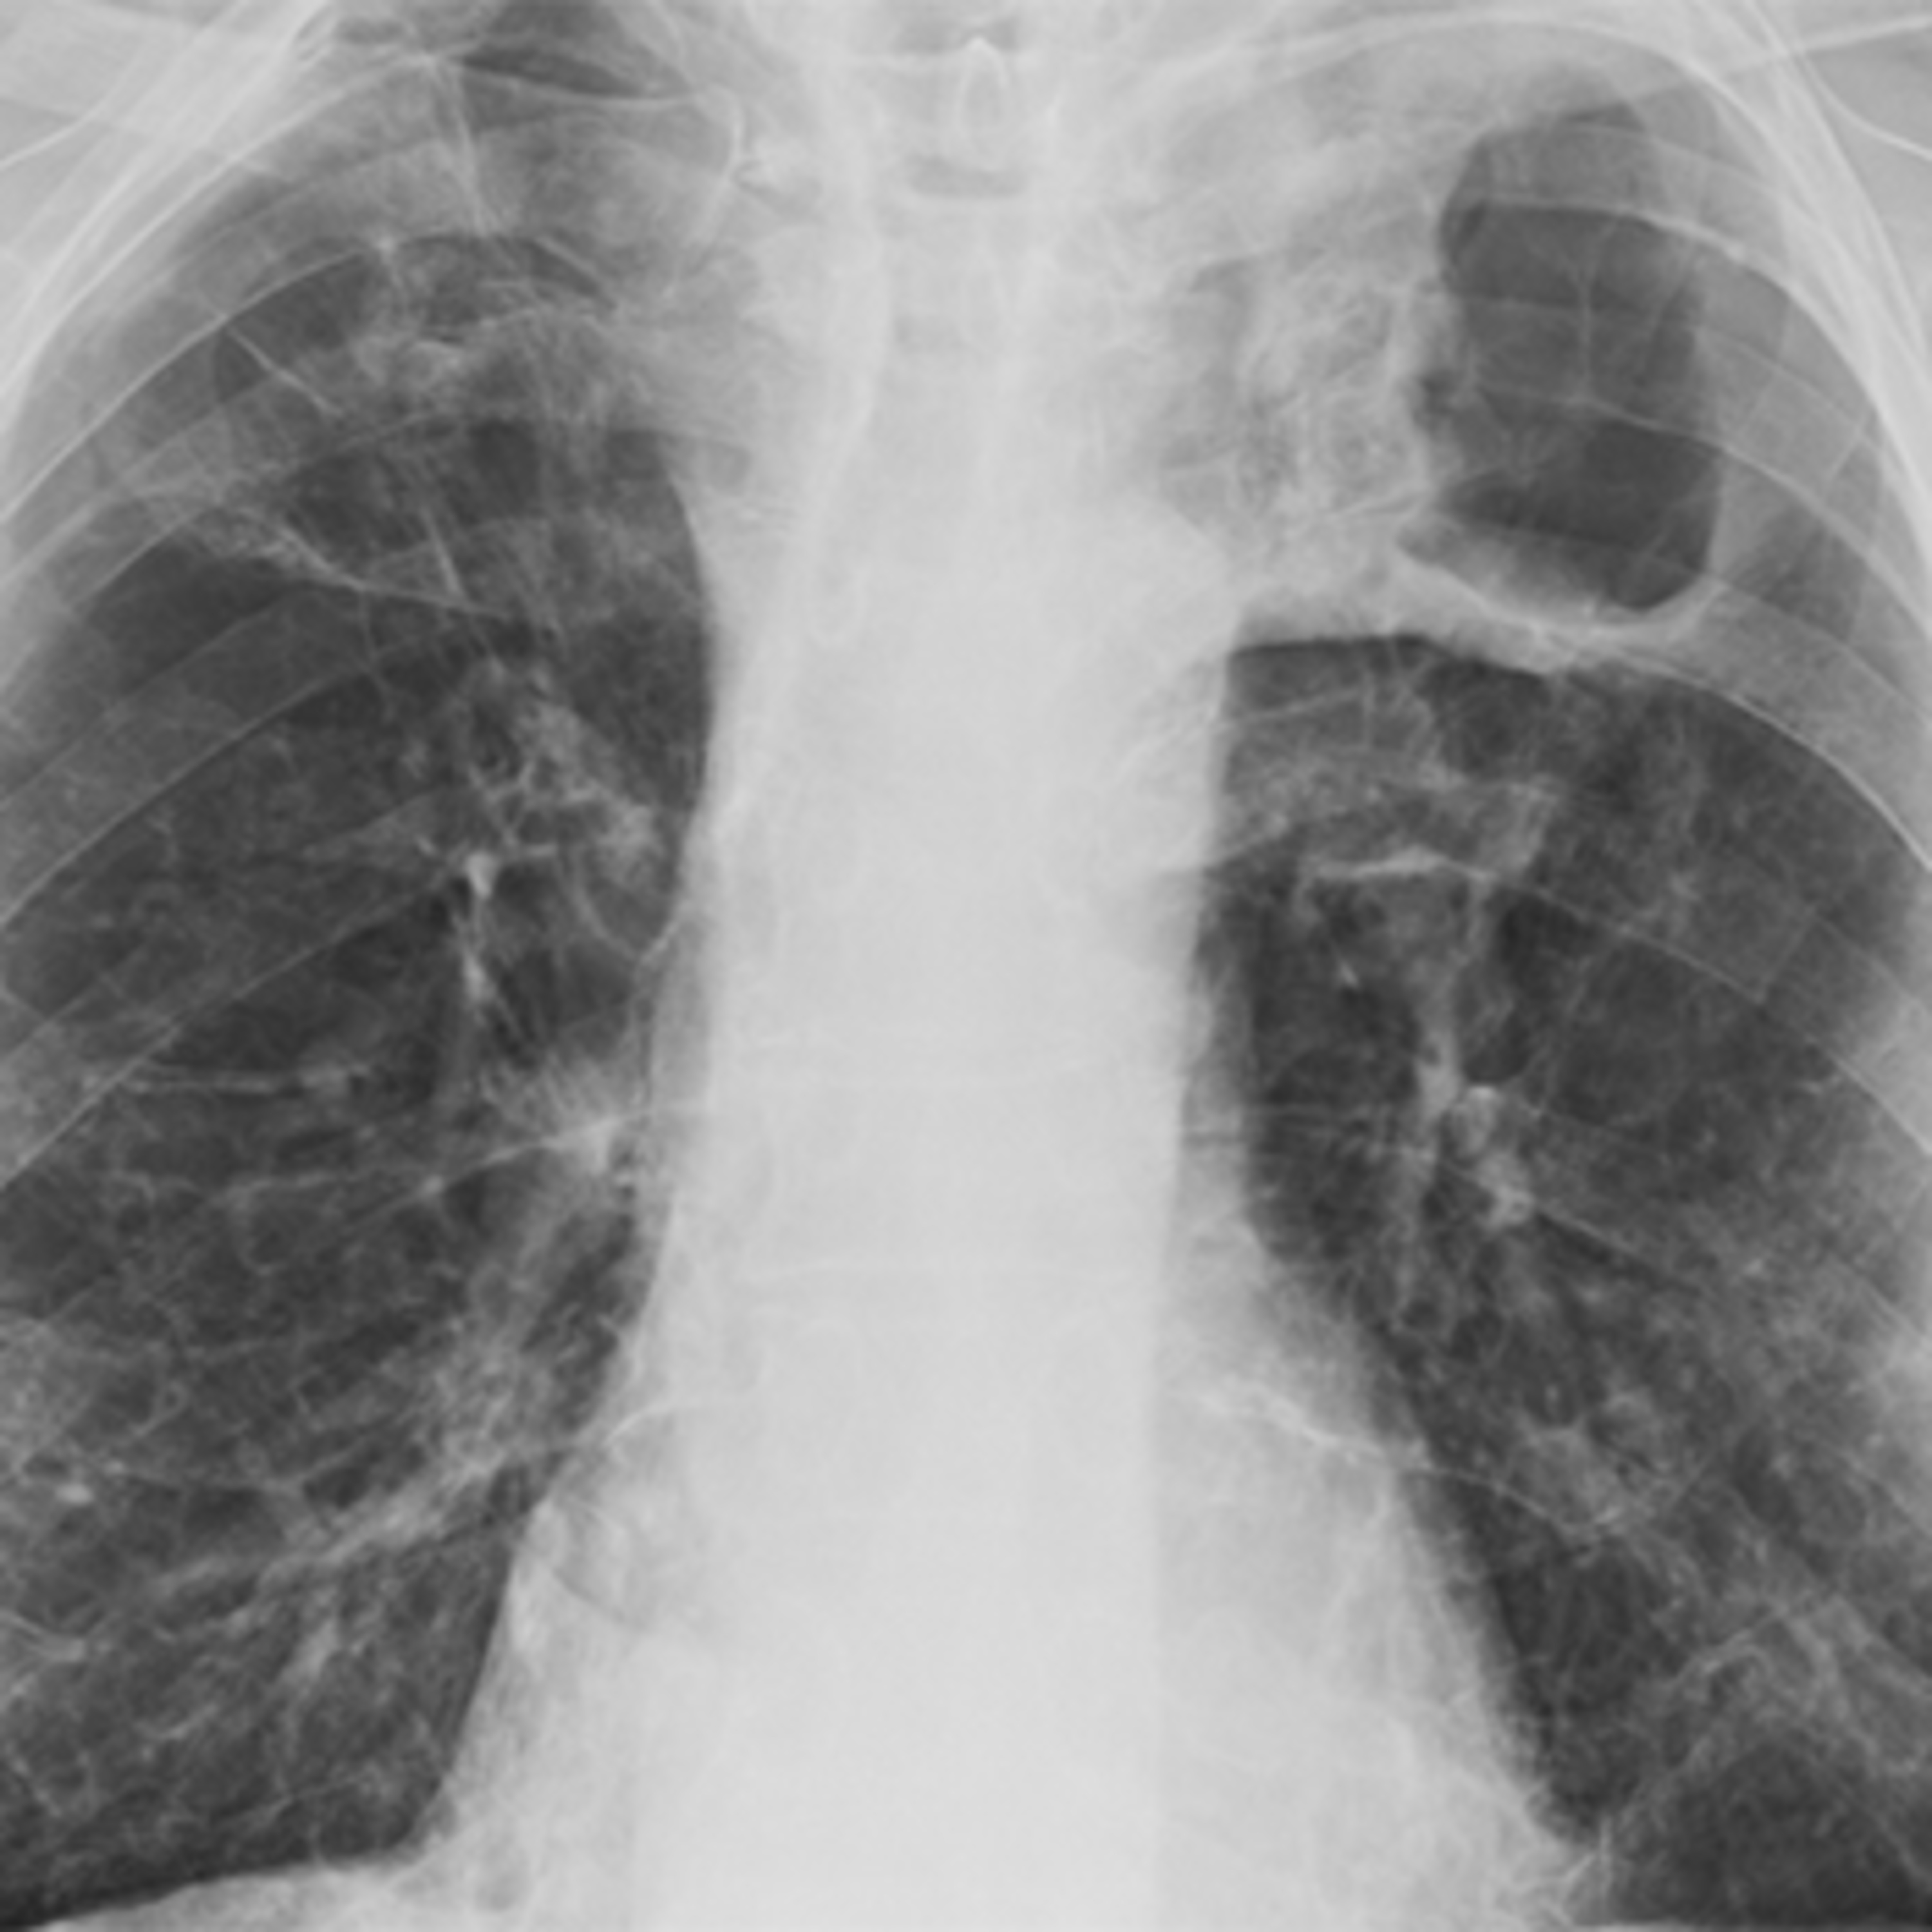

In this episode Merle and Lee speak with Eric Story (Western University) about his work on tuberculosis in the Canadian army during World War I. Eric begins by discussing disability studies and tuberculosis before focusing on the Canadian military during the war. As a social historian, Story examines the impacts of tuberculosis on different groups in Canadian society. He then expands on some of the attempts to treat tuberculosis through sanatoria while also calling attention to the fact that Canadian governments took care of soldiers’ present and future, investing substantial resources for this purpose. The conversation also includes a reflection on writing about tuberculosis during Covid, public health and the forgetting(?) of Covid.